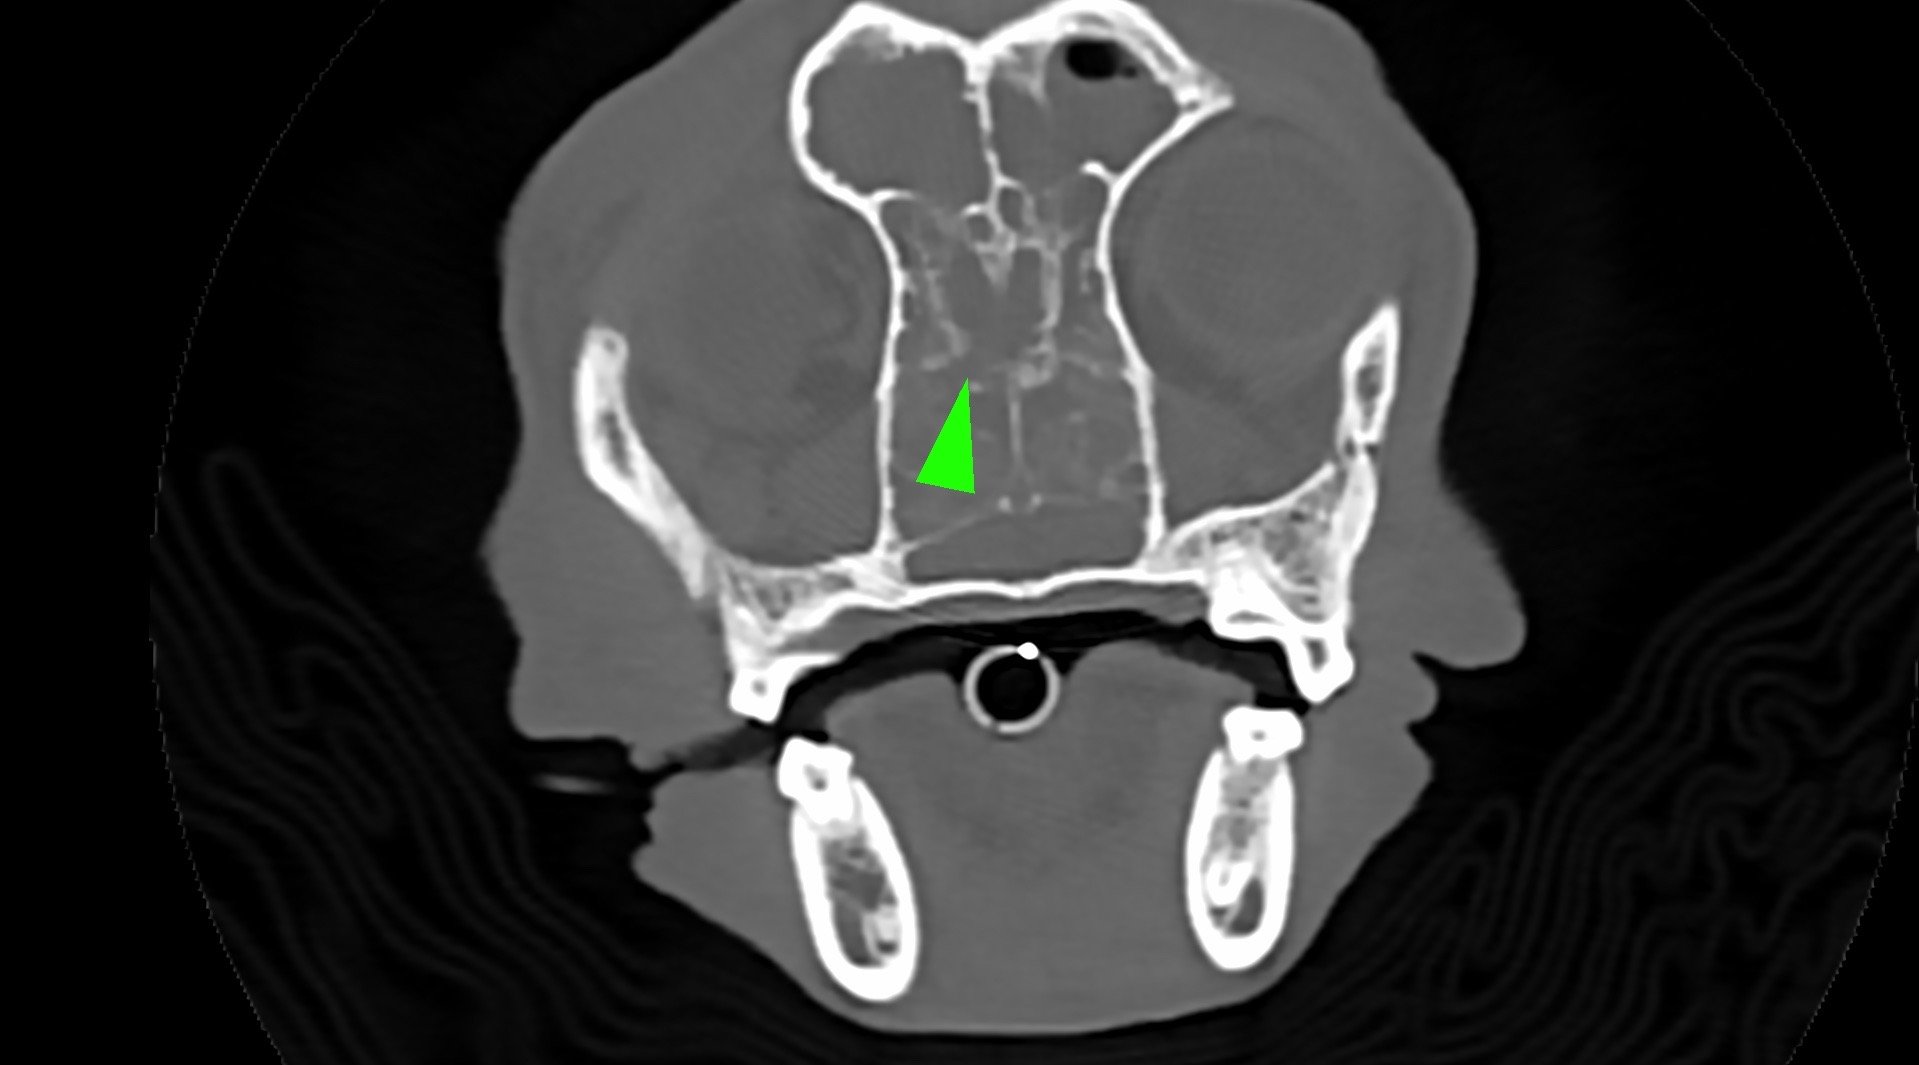

• 狗狗 鼻腔腫瘤 淋巴癌

狗狗 鼻腔腫瘤 淋巴癌